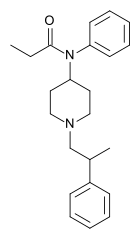

Anilidopiperidines

- 3-Allylfentanyl

- 3-Methylfentanyl

- 3-Methylthiofentanyl

- 4-Phenylfentanyl

- Alfentanil

- α-Methylacetylfentanyl

- α-Methylfentanyl

- α-Methylthiofentanyl

- Benzylfentanyl

- β-hydroxyfentanyl

- β-hydroxythiofentanyl

- β-Methylfentanyl

- Brifentanil

- Butyrfentanyl

- Carfentanil

- Fentanyl

- Lofentanil

- N-Methylcarfentanil

- Mirfentanil

- Ocfentanil

- Ohmefentanyl

- Parafluorofentanyl

- Phenaridine

- R-30490

- Remifentanil

- Sufentanil

- Thenylfentanyl

- Thiofentanyl

- Trefentanil

Structures